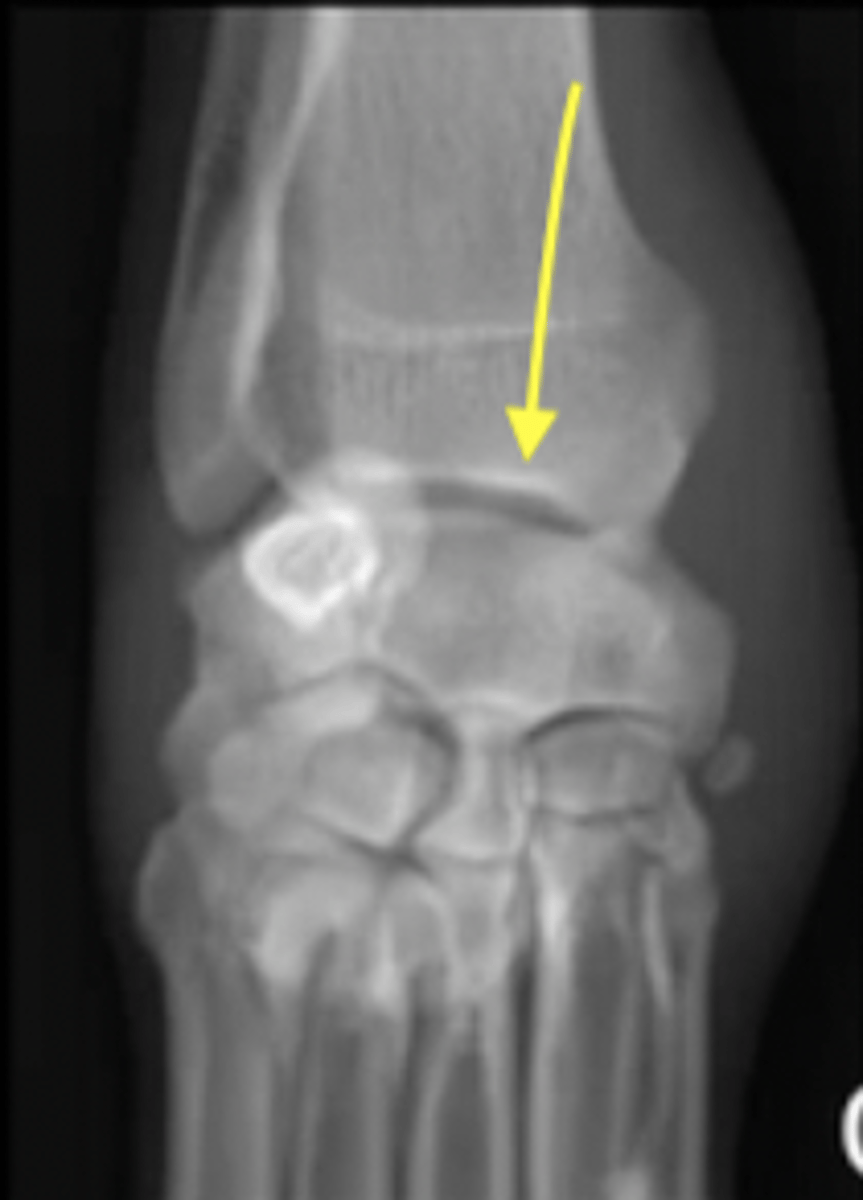

What is the arrow pointing to?

foramen for a nutrient blood vessel

What are the arrows pointing to?